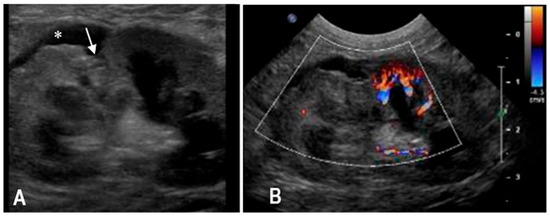

3.2. Case 2